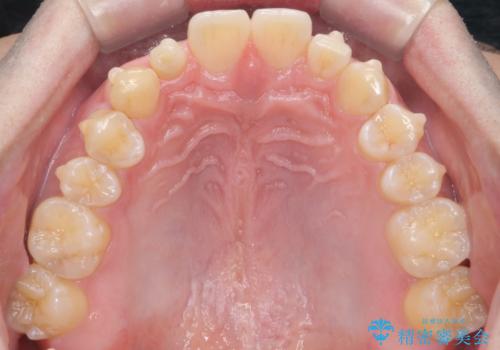

- インビザライン(マウスピース矯正)

- 治療期間

- 11ヶ月

矯正治療で1番目の歯を寄せて2番目の歯はセラミックで形をととのえています。